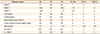

Table 1

Measurements from lateral cephalograms acquired before treatment (T0), after a 20-month treatment period (T1), and after a 24-month retention period (T2) for a young girl with severe Class III malocclusion due to maxillary hypoplasia

The patient underwent alternate rapid maxillary expansions and constrictions with a hybrid hyrax-mandibular miniplate combination and simultaneous orthodontic treatment for 20 months, followed by the retention phase.

T0, Taken at the initial visit (11 years old); T1, taken after 20 months of treatment (12 years 10 months); T2, taken after 24 months in retention (14 years 10 months); SNA, sella-nasion-A point; SNB, sella-nasion-B point; ANB, A point-nasion-B point; CoA, Condileon to A point; CoPog, condileon to pogonion; FH, Frankfort plane; Lower anterior facial height, anterior nasal spine to menton; Wits, distance between perpendiculars from A point and B point onto the occlusal plane; U1-PP, maxillary lateral incisor to Palatal plane angle; L1-MP, mandibular incisor to mandibular plane angle.